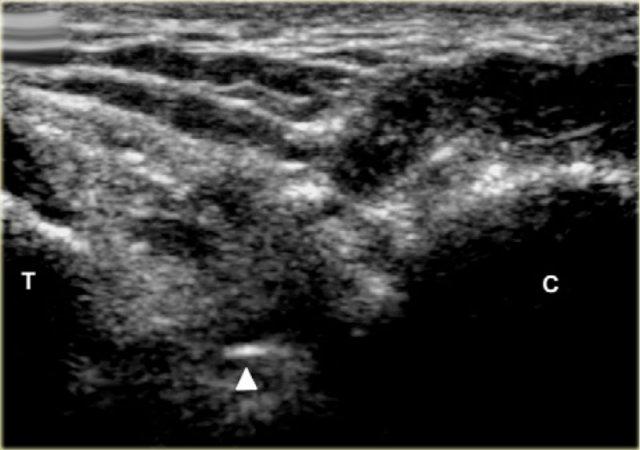

Sinus tarsi

Xoang cổ chân là một khoang hình nón chạy theo hướng từ sau-trong đến trước-ngoài. Nó nằm ở mặt ngoài của bàn chân, giữa cổ xương sên và mặt trên-trước của xương gót.

Xoang cổ chân tiếp nối về phía trong thành ống cổ chân, đây là khoang hình phễu nằm giữa xương sên và xương gót.

Nó chứa mô mỡ, một vòng nối động mạch, bao khớp, các đầu tận thần kinh và năm cấu trúc dây chằng – rễ trong, rễ giữa và rễ ngoài của mạc hãm duỗi dưới; dây chằng cổ; và dây chằng sên gót gian cốt (hình).

Khoang này có thể là nguyên nhân gây đau bàn chân trong hội chứng xoang cổ chân. Bước đầu tiên trong điều trị là tiêm thấm xoang cổ chân bằng hỗn hợp Depomedrol và thuốc gây tê tại chỗ (Lidocaine). Điều này có thể gây khó khăn cho phẫu thuật viên khi thực hiện theo phương pháp không có hướng dẫn, nhưng có thể thực hiện một cách tương đối dễ dàng và chính xác với sự hỗ trợ của siêu âm.

Tiêm dưới hướng dẫn siêu âm vào xoang cổ chân bên phải với đường vào từ phía ngoài. Đầu dò được giữ theo mặt phẳng chếch vành. Kim được đưa vào dọc theo trục dài của đầu dò.

Bệnh nhân lăn sang bên đối diện, đặt bàn chân cần điều trị với mặt trong tiếp xúc với mặt bàn, mặt ngoài của bàn chân hướng lên trên.

Đầu dò được giữ theo mặt phẳng chếch vành so với bàn chân.

Xoang cổ chân được xác định là một khoang hình tam giác nằm giữa mỏm trước của xương gót và cổ xương sên.

Đầu kim (mũi tên) được nhìn thấy trong xoang cổ chân hình nón, được giới hạn bởi xương sên (T) và xương gót (C).

Tùy thuộc vào mức độ viêm, có thể có hiện tượng xung huyết trong khoang và có thể thấy các mạch máu xen kẽ, những mạch máu này cần được tránh. Điều này tương đối dễ dàng, đặc biệt khi sử dụng doppler màu